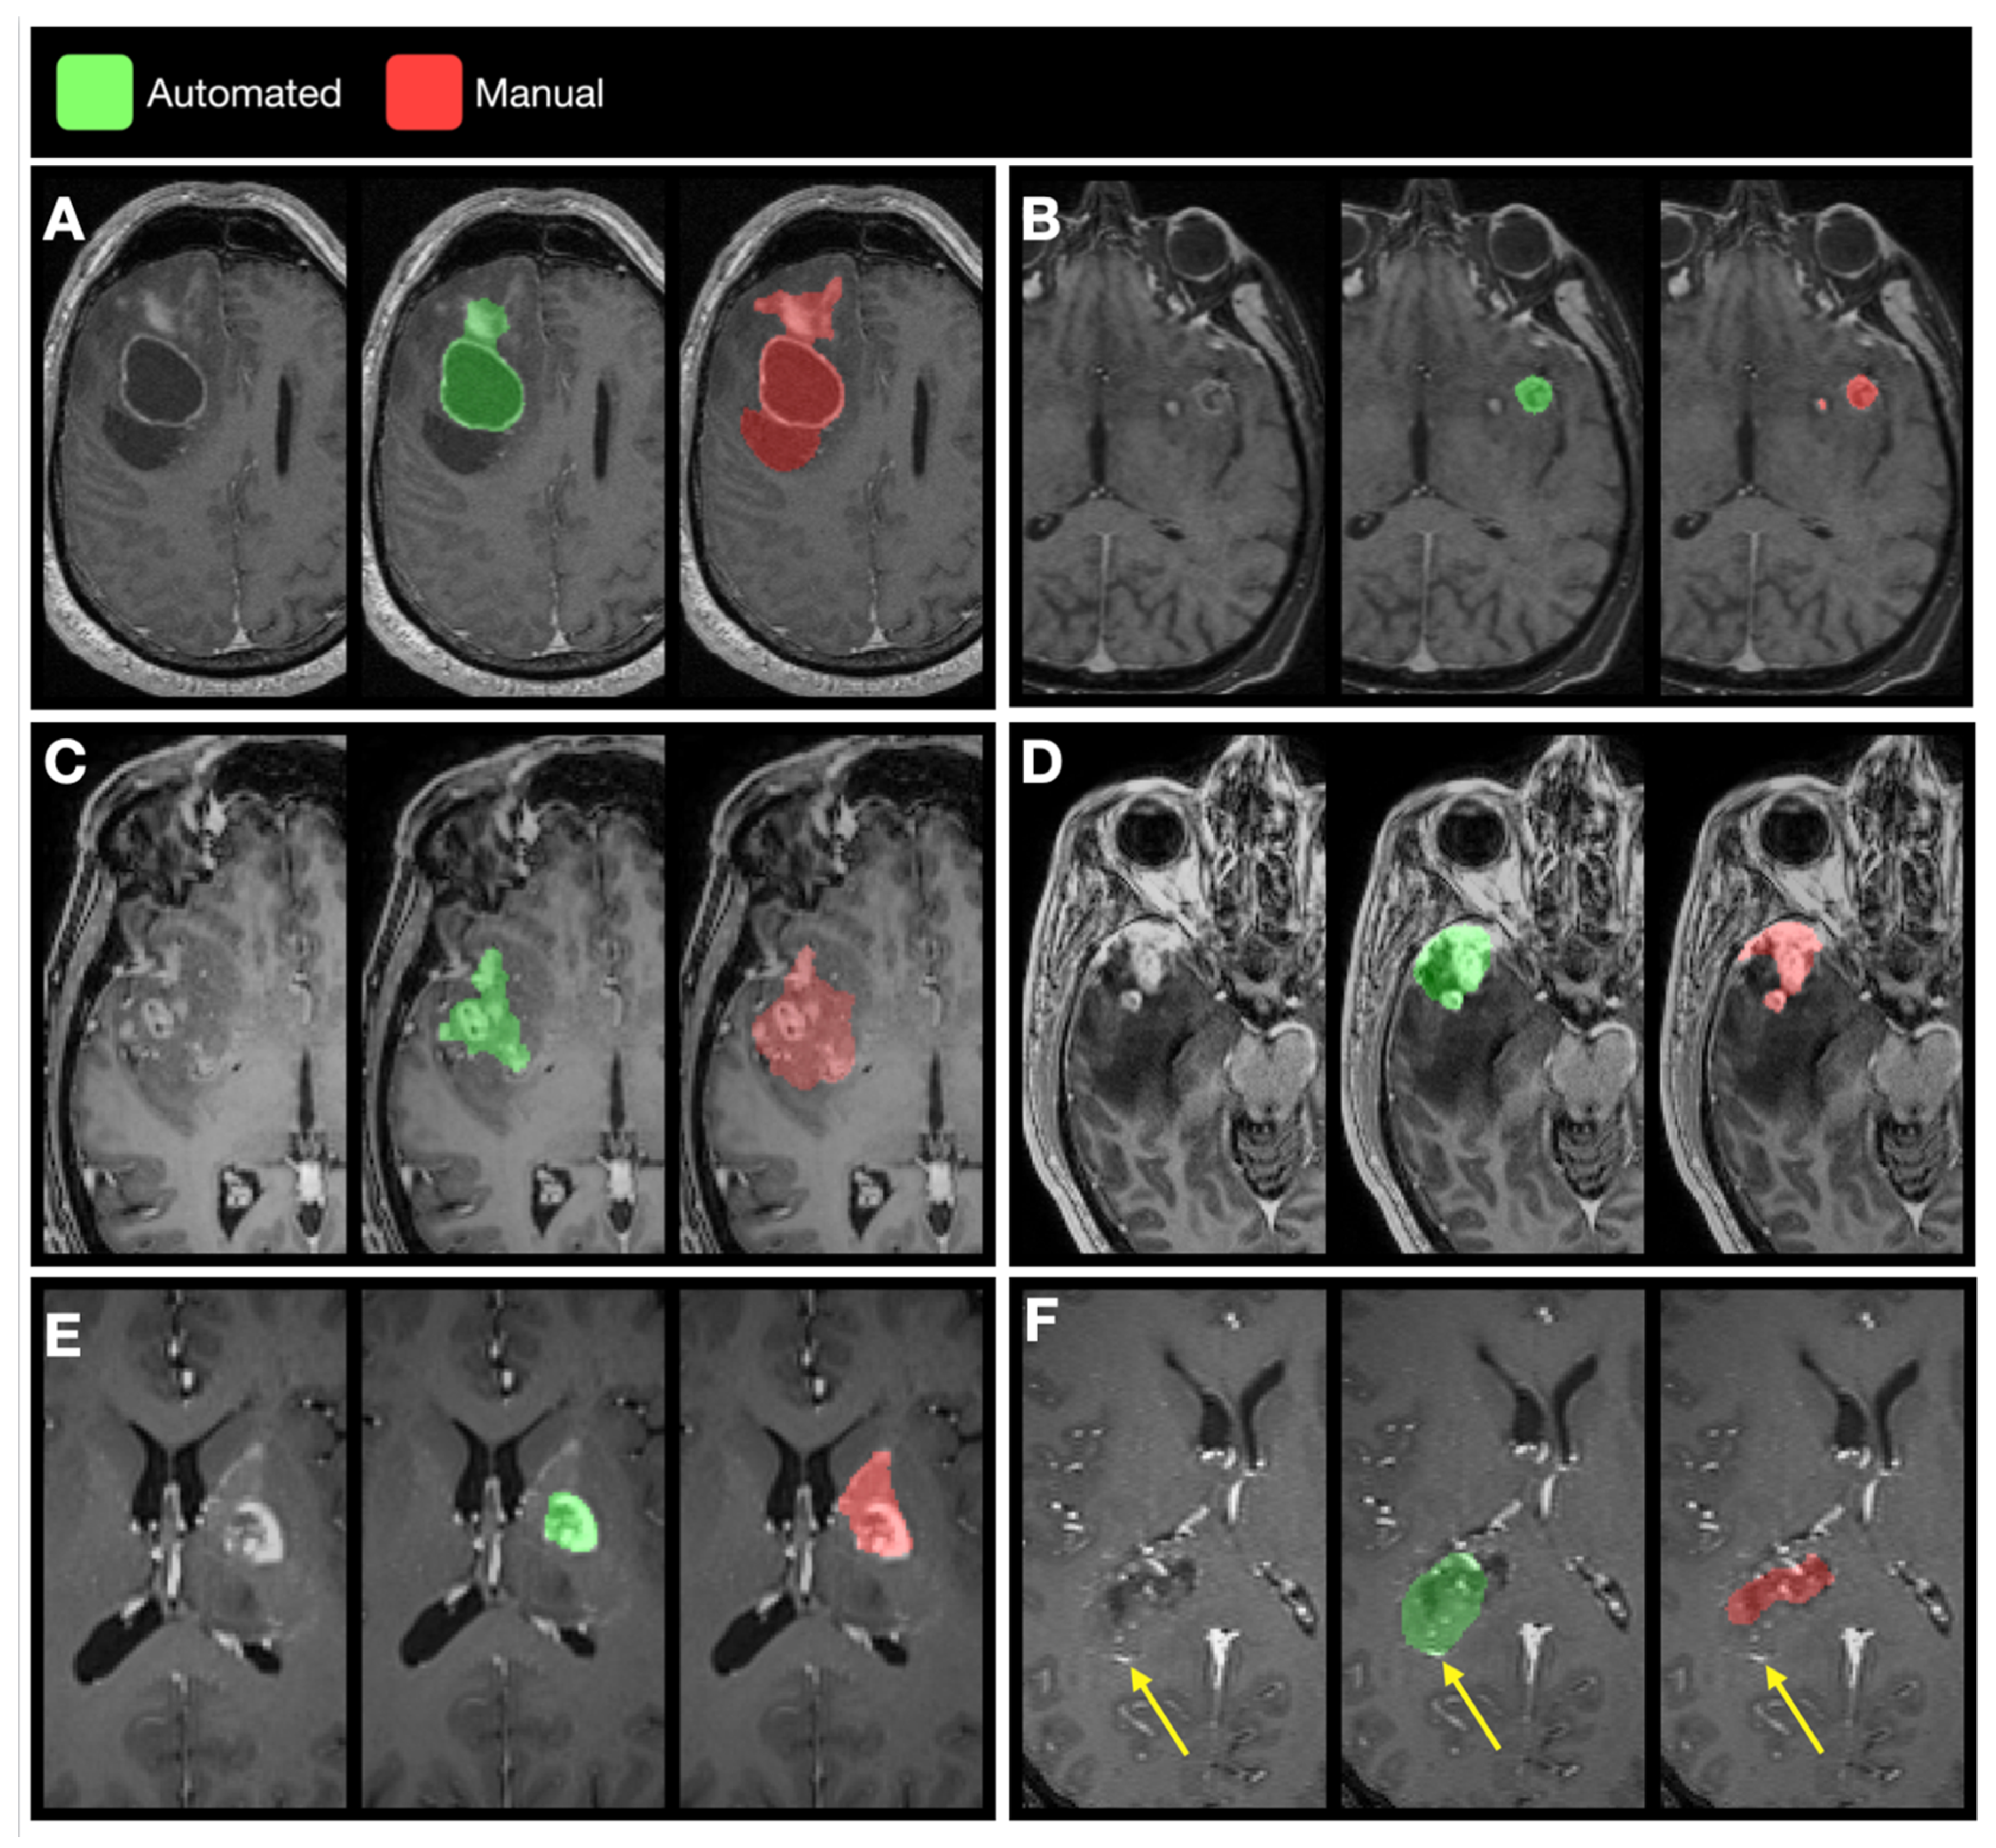

3.3. Examples of Disagreement between Manual and Automated Segmentations